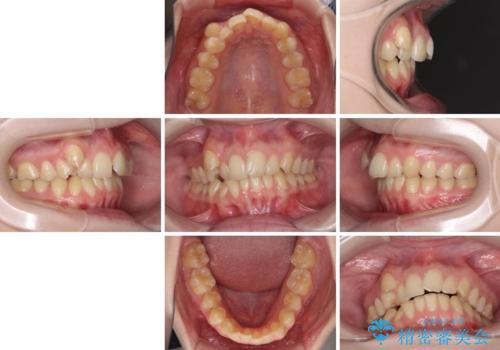

- 著しい八重歯を気にして来院された患者様です。

片側の八重歯であり上顎の正中がずれていたため、上顎左右第一小臼歯2本を抜歯して排列することとしました。

下顎の骨格的なズレが大きかったため、上下歯列のバランスが取れるか心配でしたが、上下ともに左右対称に近い歯列で治療を終えることができました。